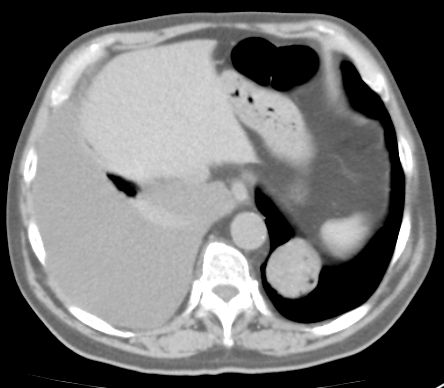

72-jähriger Mann mit einem 4cm großen Rundherd im linken Unterlappen. Der Befund ist seit 5 Jahren konstant. Jetzt zentrales Adenokarzinom rechts mit Pleuraerguss. ![]() | |||